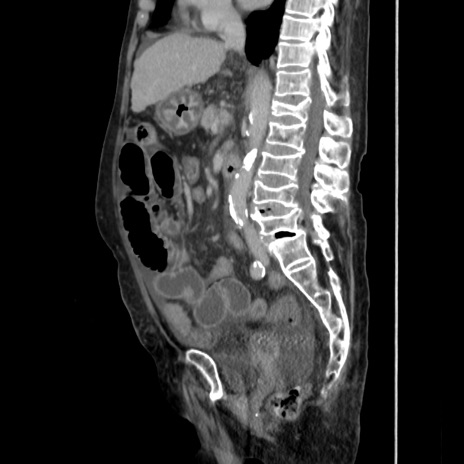

冠状断像

【症例】80歳代 女性

【主訴】腹部膨満感

【現病歴】他院にて肝硬変にてフォロー中。1週間前から便秘、腹部膨満感、臍部腫瘤あり受診となる。

【既往歴】肝硬変

【身体所見】腹部膨隆あり、皮膚変化なし、疼痛なし。

【データ】WBC 4600、CRP 0.25